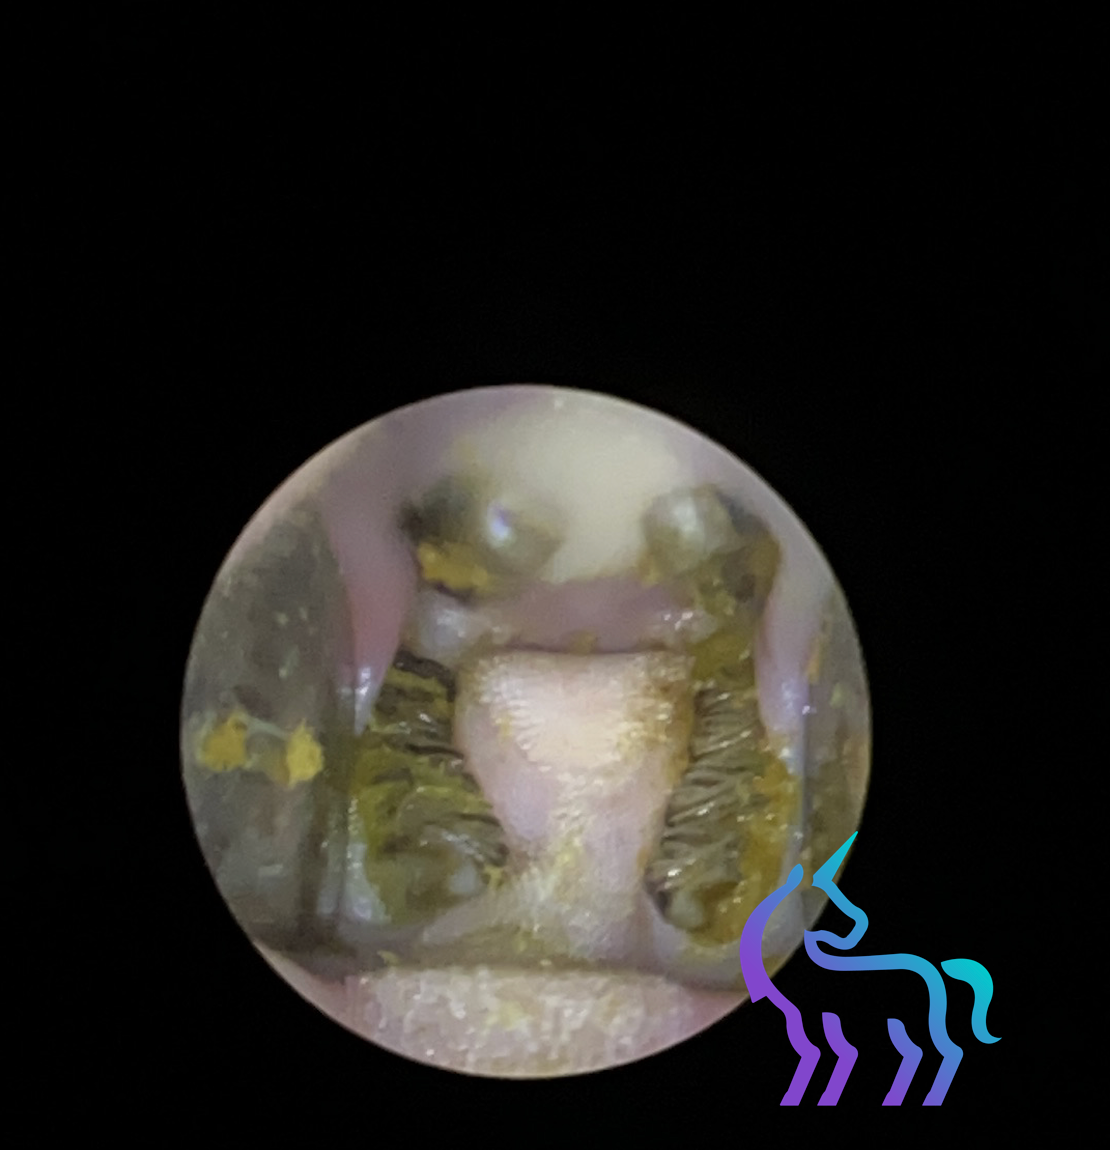

Explorez nos cas cliniques en vidéo-otoscopie. Cette technologie haute définition nous permet d’explorer avec une précision inédite les NAC et les reptiles, là où l’examen classique atteint ses limites.